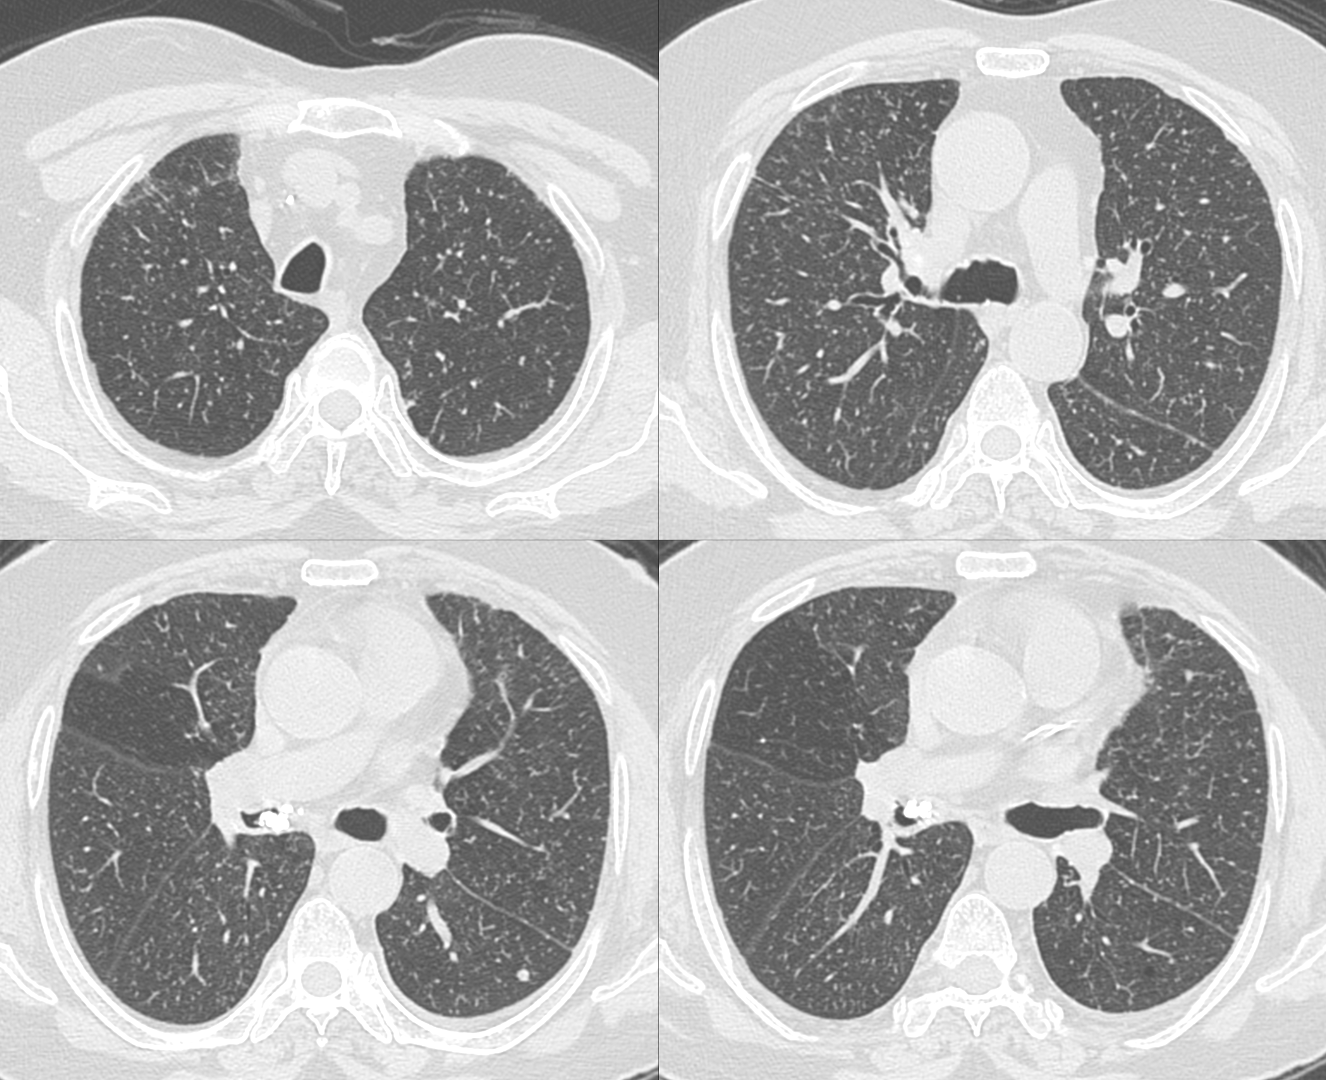

71-years old man with fever.

CT shows miliary nodules likely due to miliary tuberculosis.

It also shows a calcified subcarinal node extending into the intermediate bronchus.